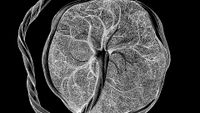

A new map of the "maternal-fetal interface" reveals a new type of cell, as well as the types of cells most likely to be affected in conditions like preeclampsia.